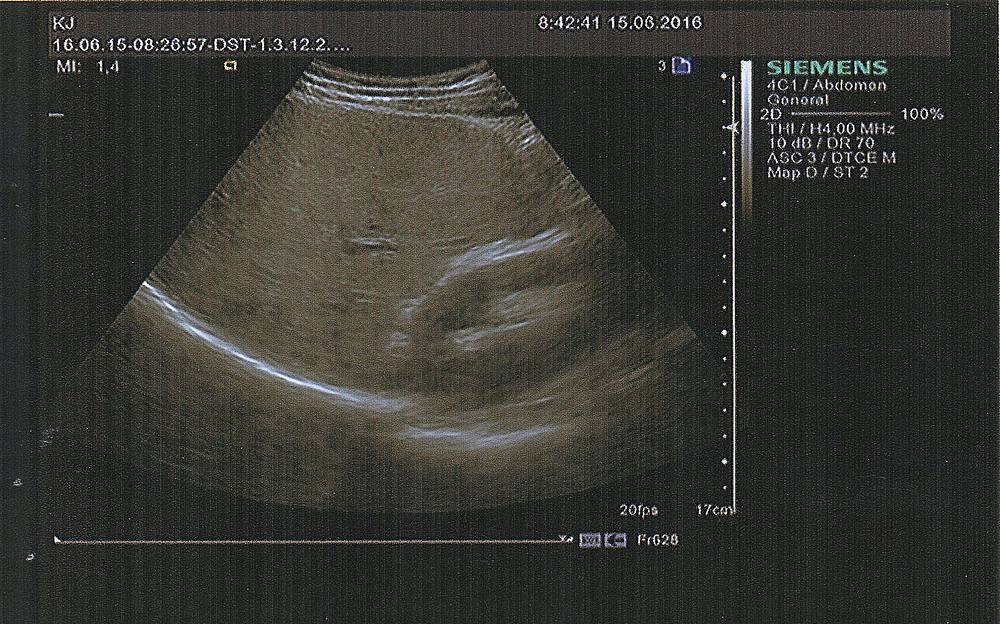

Всем -Привет ! Анализы фибротеста нифига не дали из-за невозможности составить график,низкий гаптоглобин. Мой областной гастроэнтеролог сказала ,что с Синево такое бывает .Посоветовала сделать эластографию. Сказала.что всё что там будет ,нас вполне устраивает без фибротеста,что б определить время курса Виропак Плюс / Viropack Plus (Египетский Харвони Harvoni) – новый препарат для лечения хронической формы гепатита С генотипа 1. Не требует комбинации с рибавирином и интерфероном. ....(Соф+Лед) Эти данные я Вам предоставляю,может кто ,что нибудь мне тоже по этим показателям поведает...Кто шарит,цирроз есть или таки ещё можно бросить вызов и сказать гепатиту нет ! ?